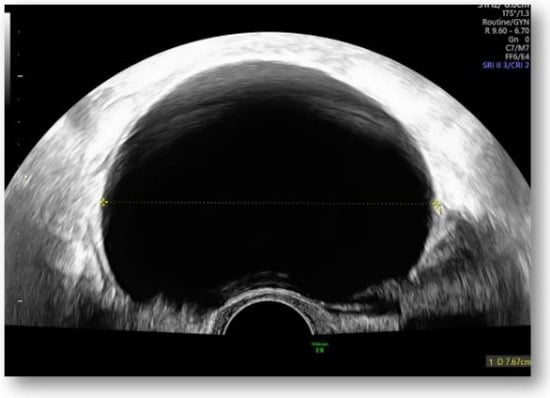

Considering all the information gathered, we first decided to perform an ultrasound (US) which revealed a large hypoechoic cystic formation on the left of the uterus, misdiagnosed as a paraovarian cyst measuring 80 mm (Figure 1, Figure 2, Figure 3 and Figure 4).

Figure 1.

Large hypoechoic cystic formation located to the left of the uterus measuring 80 mm.